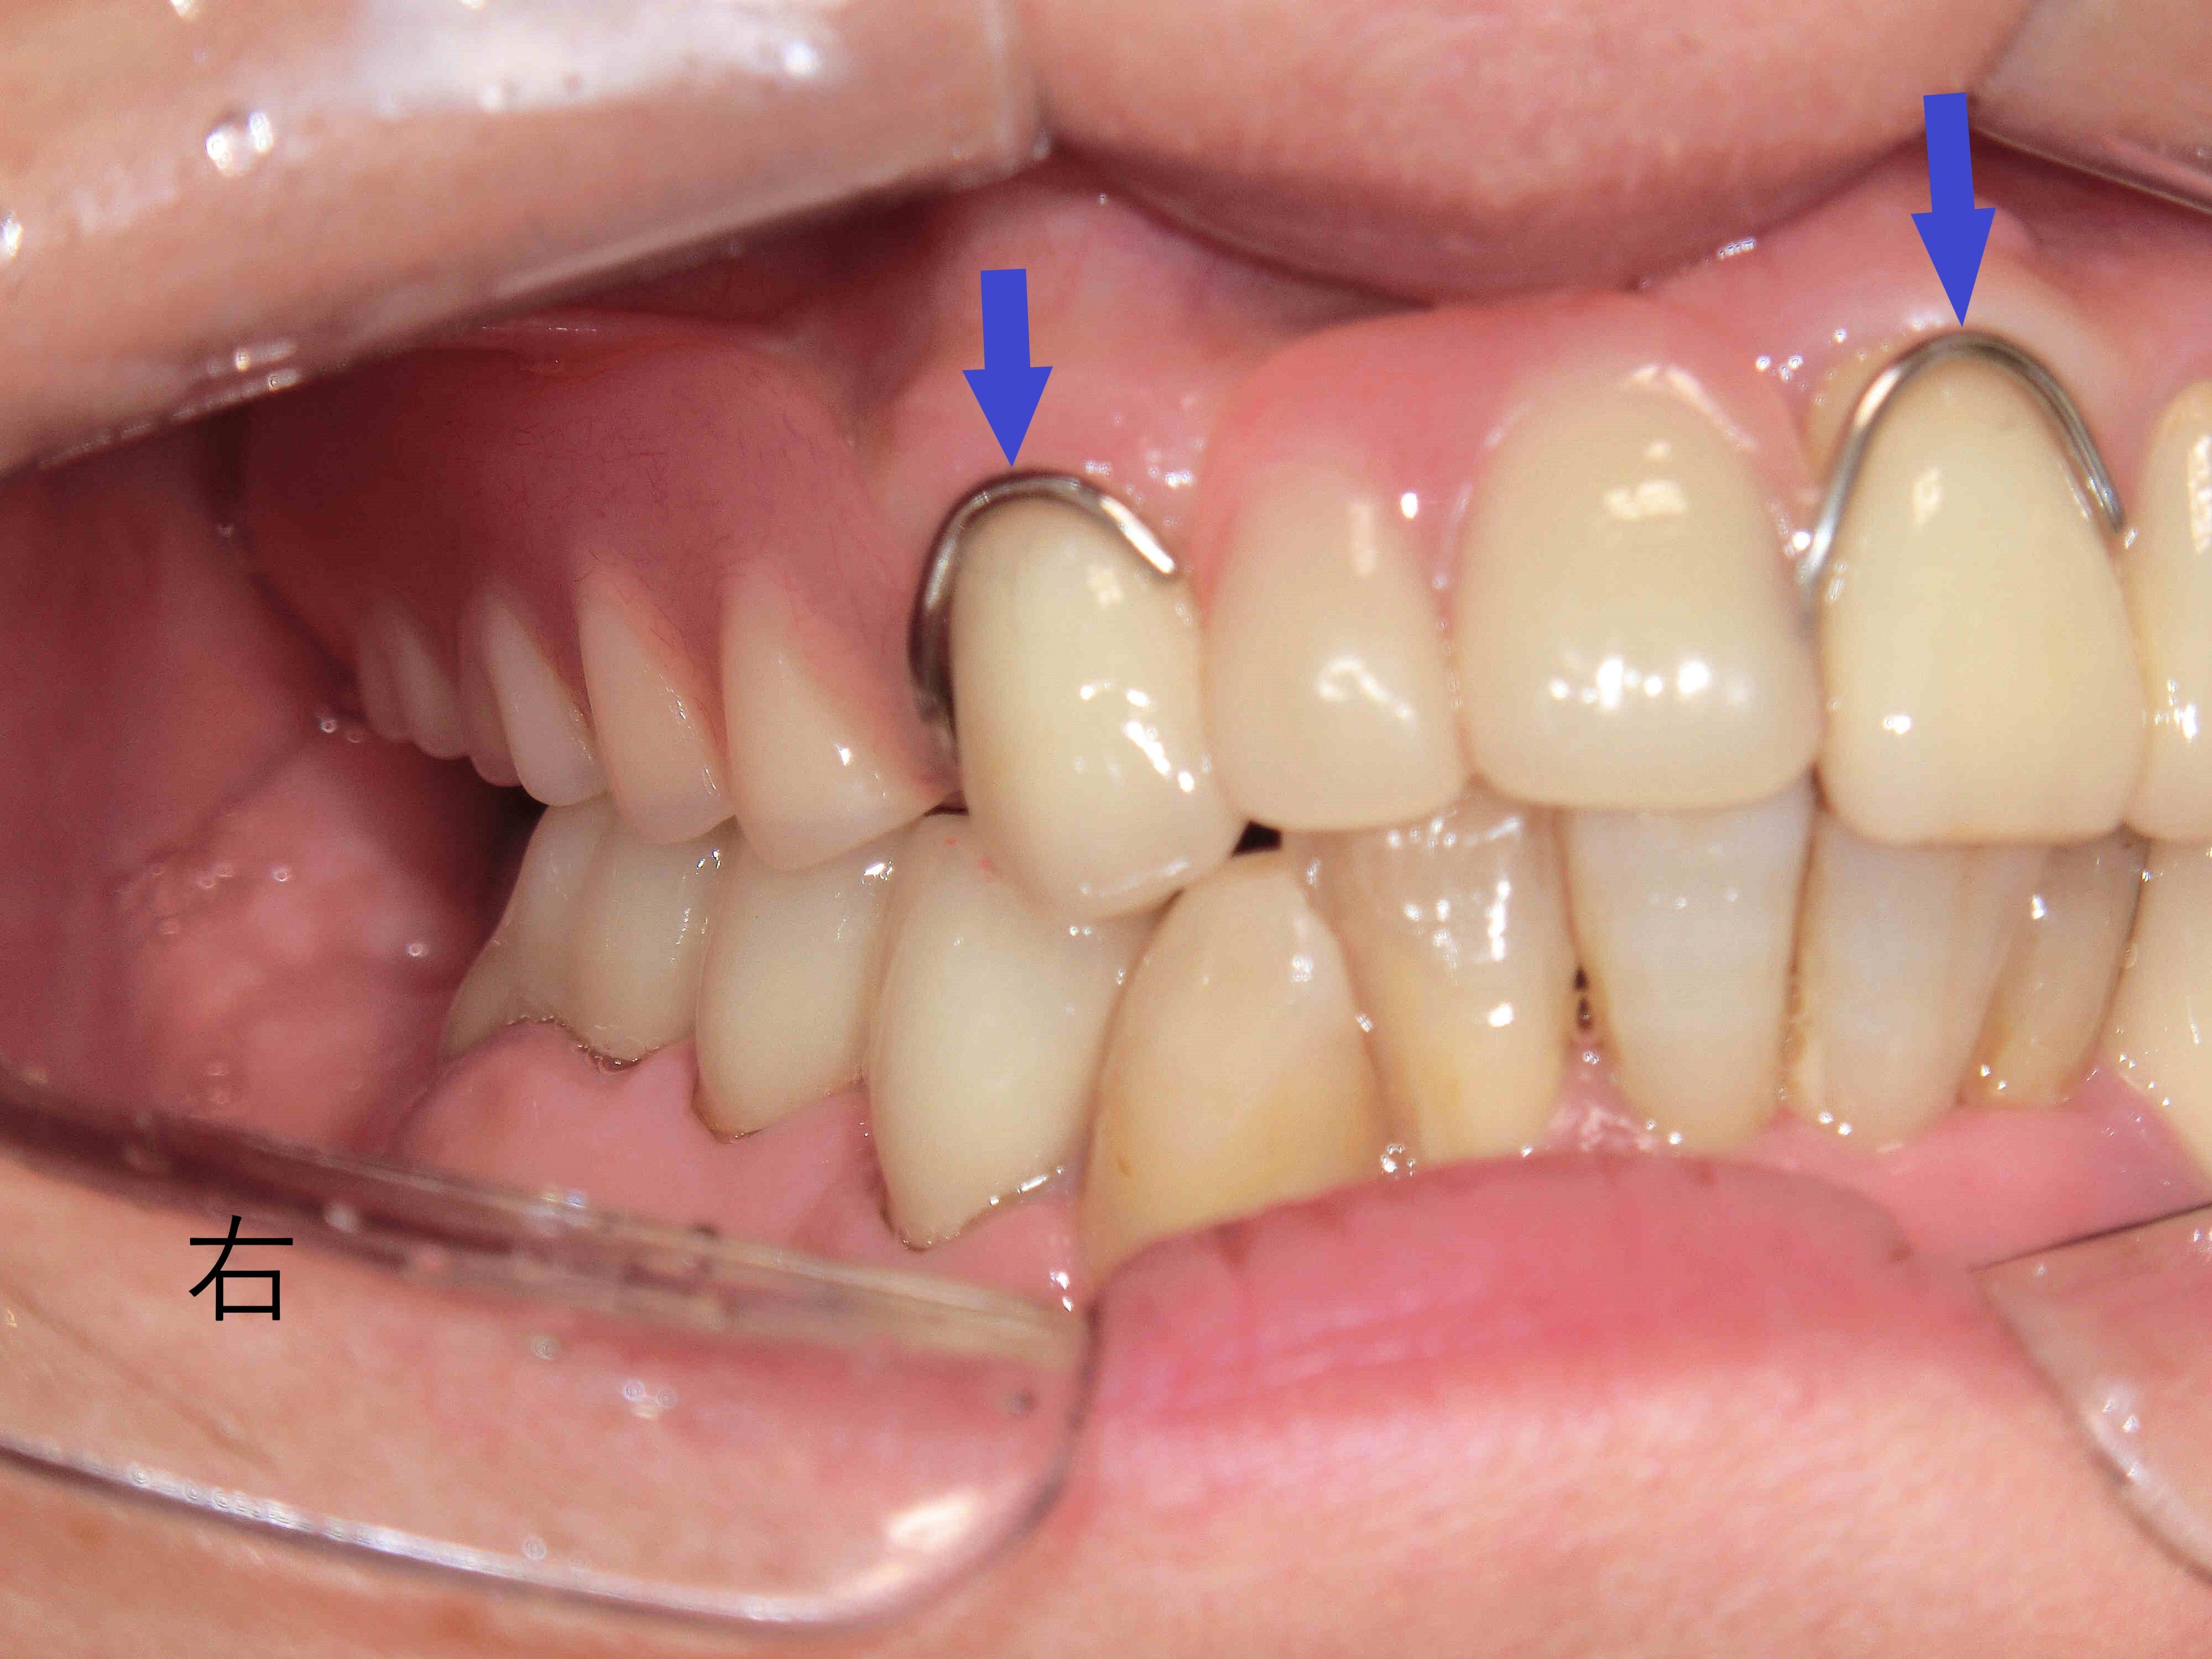

上顎に金属のバネを使用しないノンクラスプデンチャーを装着した状態を正面から撮影した写真では、歯ぐきと似た色の樹脂製のバネが用いられており、前述の保険義歯と比較して審美性が大幅に向上しています(青色矢印)。

また、口蓋部には保険義歯に使用される樹脂ではなく、チタン製の金属床が用いられており、義歯を薄く仕上げることができています。

患者様からも「薄くなって話しやすくなり、違和感が少なくなった」との感想をいただいております(※個人の感想です)。